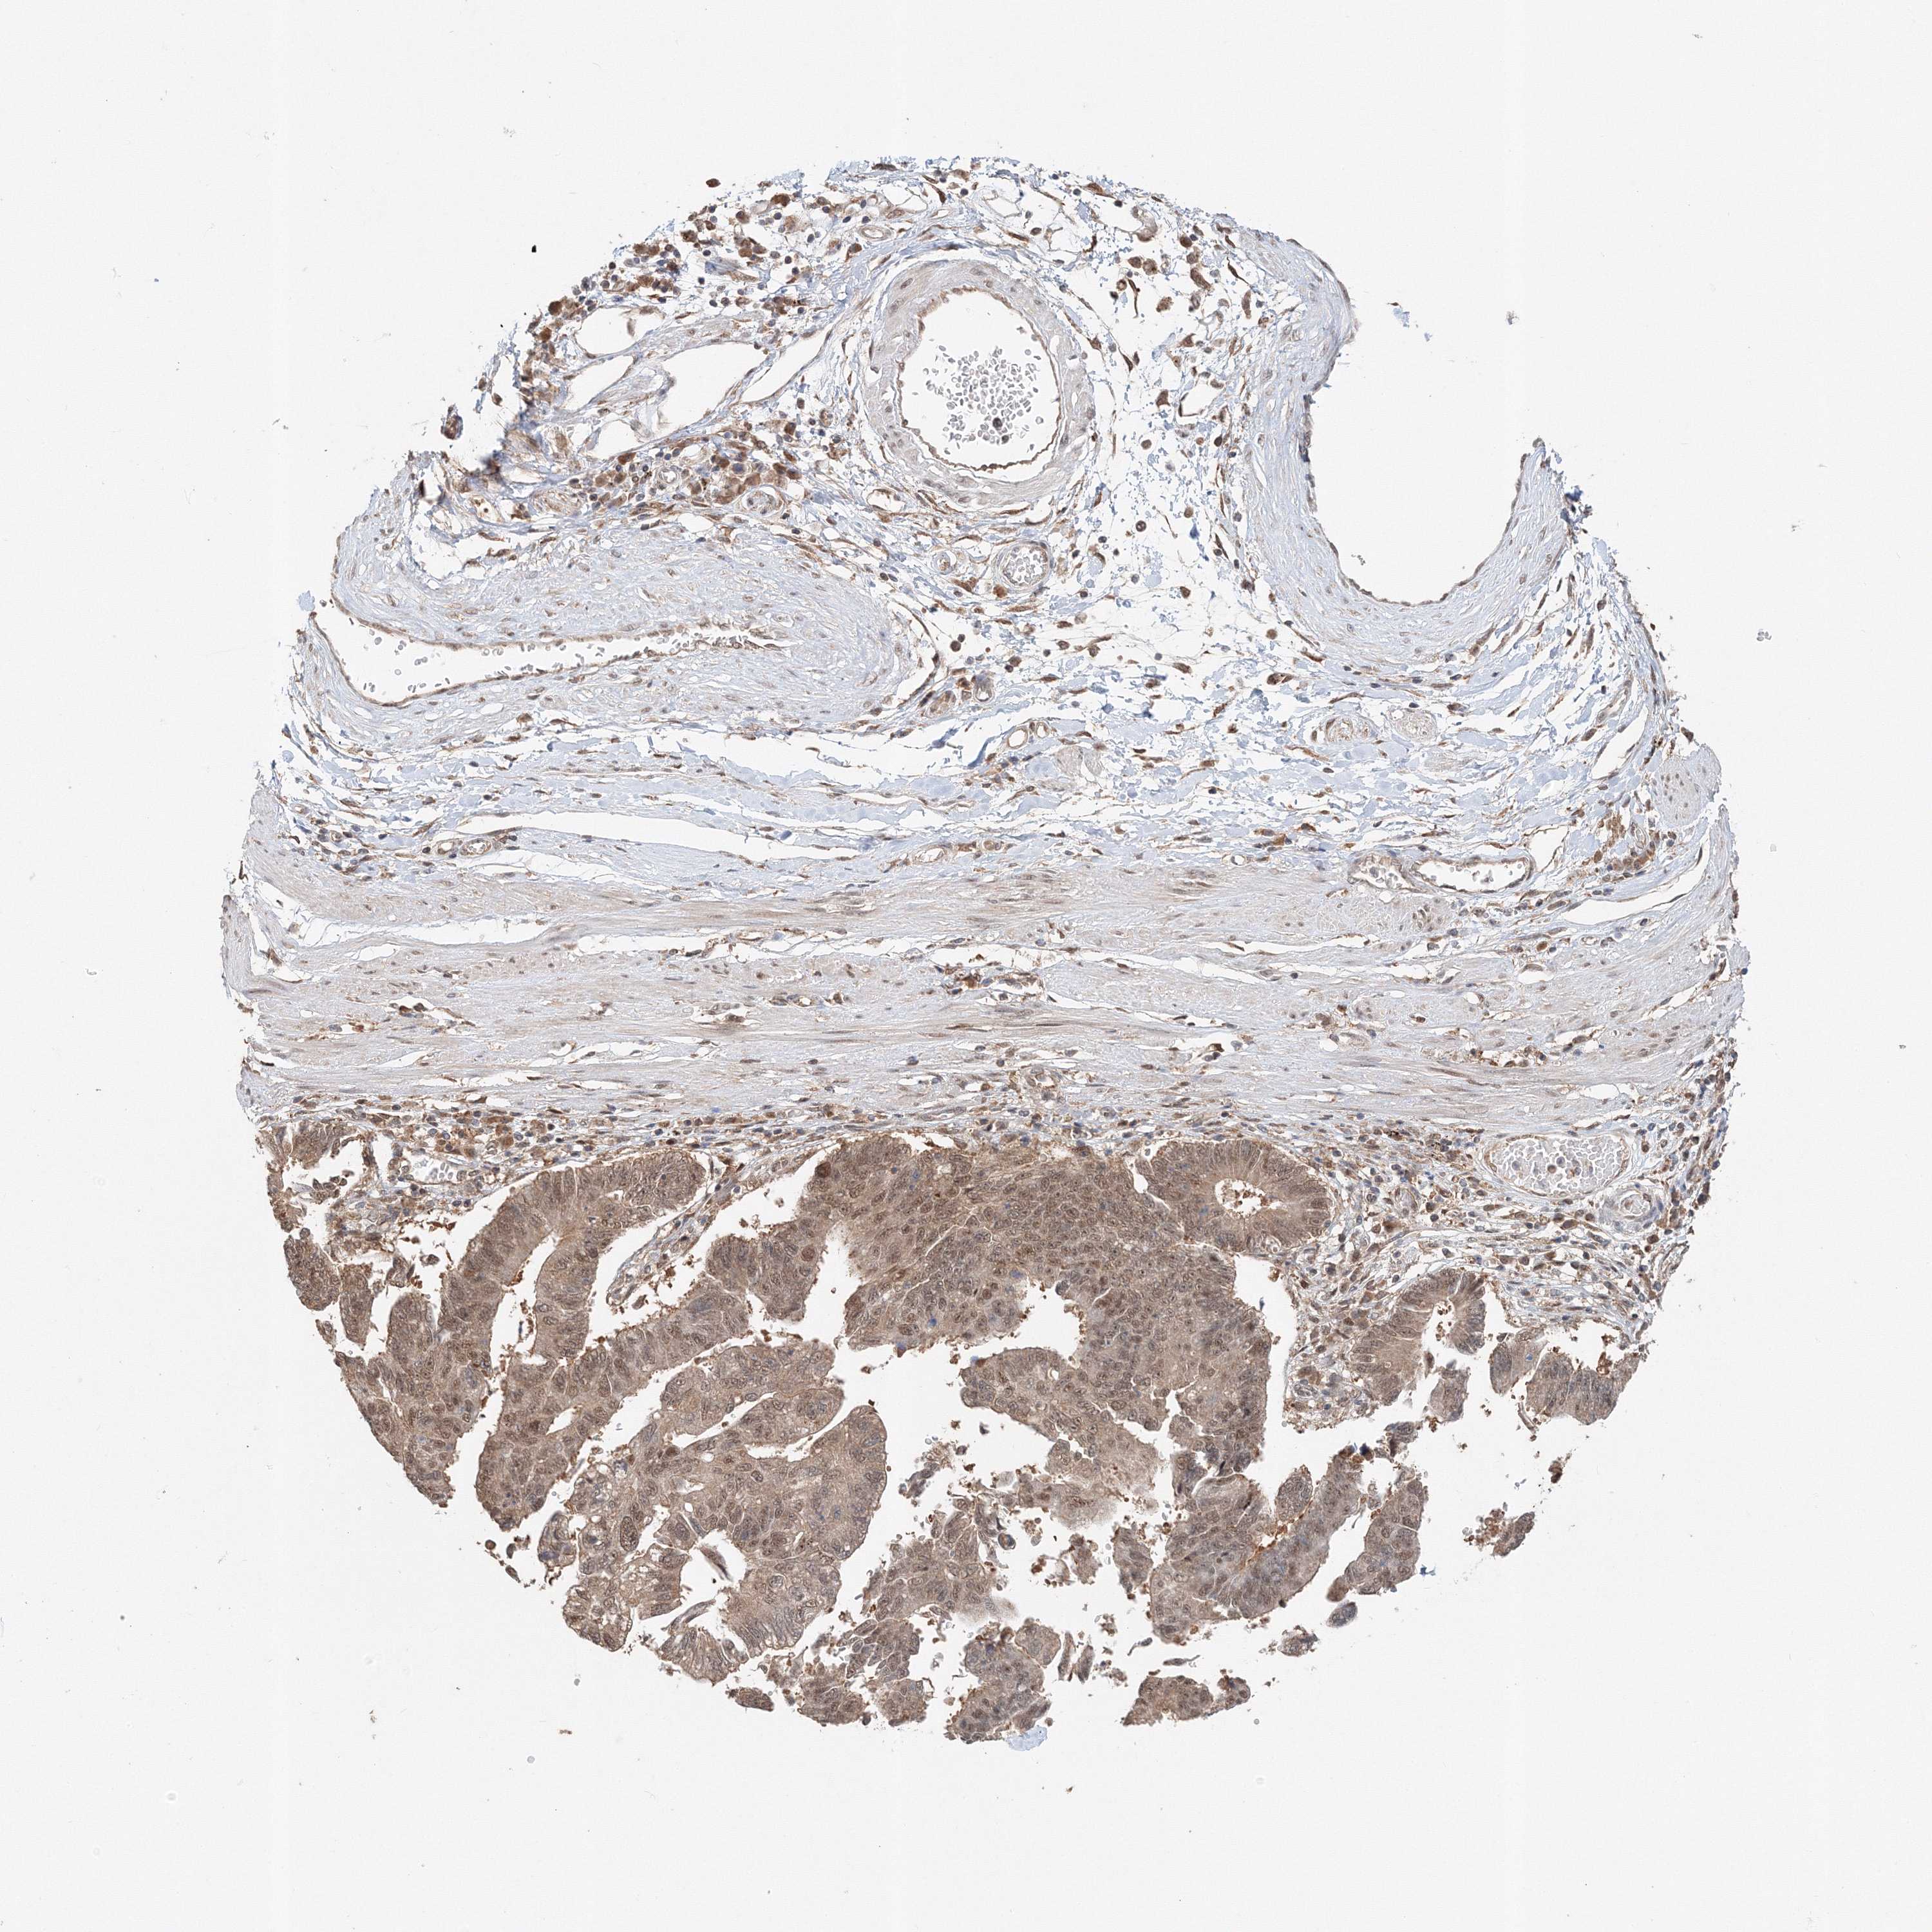

STOMACH CANCER - Protein expressioni

A mouse-over function shows sample information and annotation data. Click on an image to view it in a full screen mode. Samples can be filtered based on level of antibody staining by selecting one or several of the following categories: high, medium, low and not detected. The assay and annotation is described here.

Note that samples used for immunohistochemistry by the Human Protein Atlas do not correspond to samples in the TCGA dataset.

Antibody stainingi

Antibody staining in the annotated cell types in the current human tissue is reported as not detected, low, medium, or high, based on conventional immunohistochemistry profiling in selected tissues. This score is based on the combination of the staining intensity and fraction of stained cells.

Each image is clickable and will lead to virtual microscopy that enables deeper exploration of all samples and also displays staining intensity scores, fraction scores and subcellular localization as well as patient and tissue information for each sample.

Antibody HPA036921

Antibody HPA036922

Staining

High

Medium

Low

Not detected

Intensity

Strong

Moderate

Weak

Negative

Quantity

>75%

75%-25%

<25%

None

Location

Nuclear

Cytoplasmic/membranous

Cytoplasmic/membranous,nuclear

Adenocarcinoma, NOS